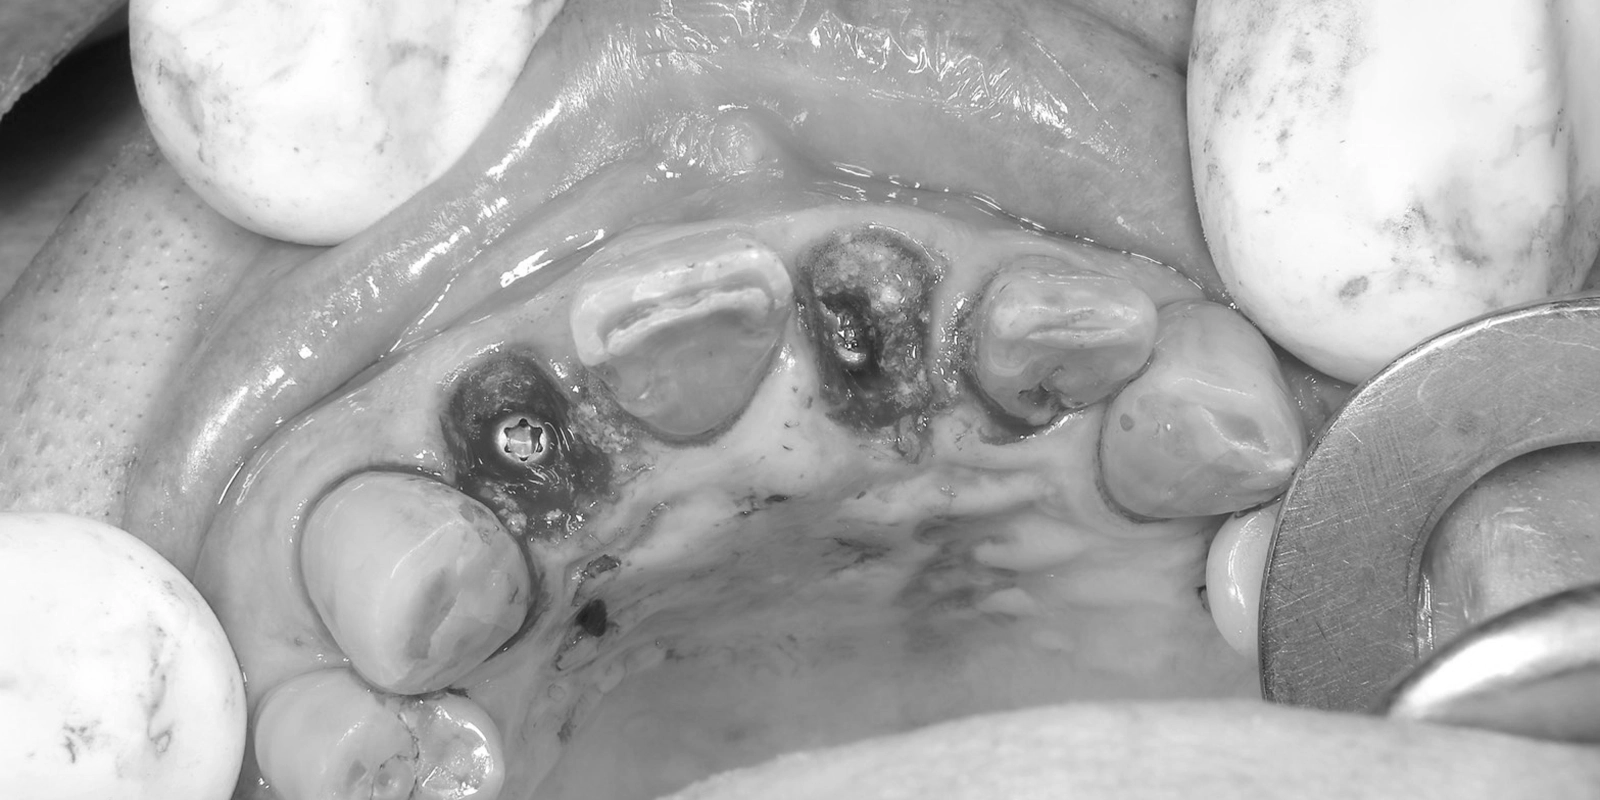

治療前の口腔内写真を確認すると、上顎前歯部には変色した大きな被せ物が複数装着されており、歯肉の広い範囲にわたって赤みと腫れが認められました。慢性的な炎症が長期間にわたって続いていた状態と考えられました。

レントゲン写真でも、前歯部(右上2番・左上1番)の歯根周囲の状態から、これらの歯を保存することが難しいと判断しました。

一方で、周囲の骨の状態を確認したところ、抜歯と同時にインプラントを埋め込むための条件が整っていると判断できたため、できる限り骨や歯肉へのダメージを最小限に抑える治療として、抜歯したその日にインプラントを埋め込む「抜歯即時埋入」を選択しました。